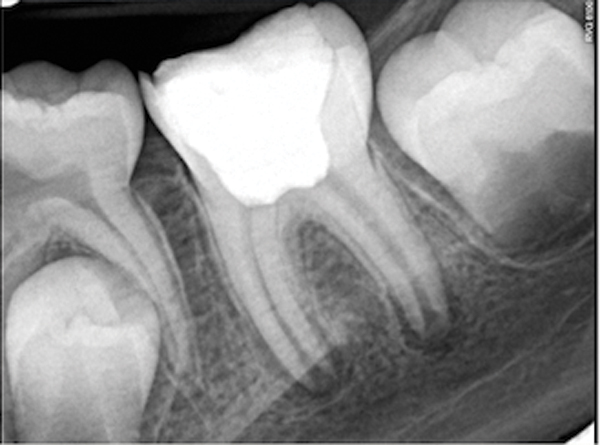

In this case, the tooth tested vital but showed clinical signs of irreversible pulpitis. Treatment with a full pulpotomy was chosen to improve the chances the remaining pulp would survive and remain healthy. The preoperative radiograph in Figure 11 shows extensive caries in the tooth and a slightly widened apical periodontal ligament. A full pulpotomy was performed using the BC putty (Figure 12). After the putty set, a coronal restoration was placed, and an immediate postoperative radiograph was taken and viewed. At the 1-year follow-up, the tooth was asymptomatic, and the radiograph showed continued root development (Figure 13), a healthy apical periodontium, and, importantly, no calcifications in the remaining pulp (as is often seen with a calcium hydroxide therapy). A radiograph taken of the contra-lateral tooth showed similar root development (Figure 14).

Figure 11. Preoperative radiograph. Courtesy of Dr. Guillaume Jouanny.

Figure 11

Figure 12. Postoperative radiography after full pulpotomy was performed. Courtesy of Dr. Guillaume Jouanny.

Figure 12

Figure 13. Tooth was asymptomatic at 1-year follow-up. Courtesy of Dr. Guillaume Jouanny.

Figure 13